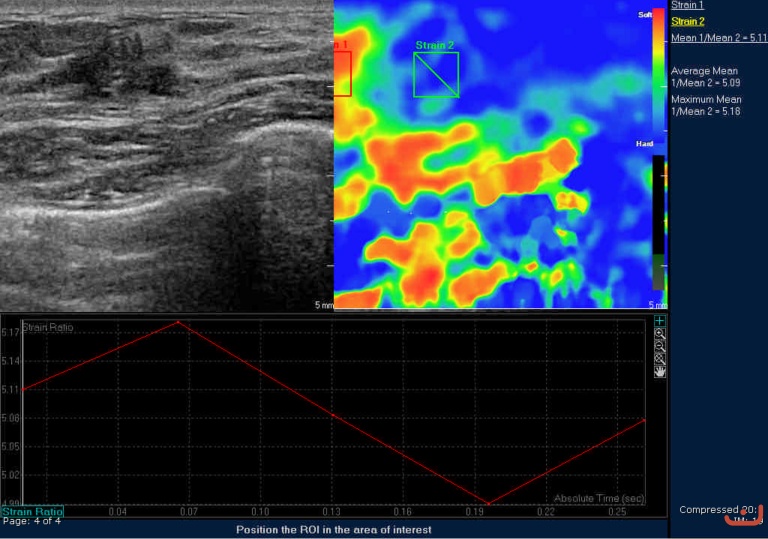

Case 49-E1

Malignant solid mass

Friday, 22 May 2015

276.55 KB (768 x 539 px)